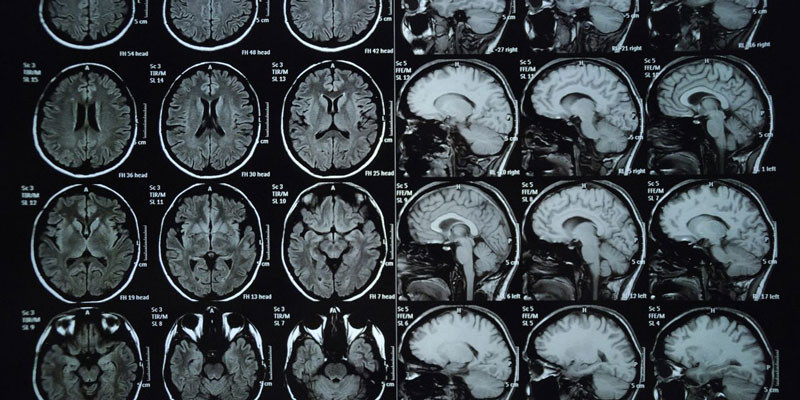

U não là sự tăng lên và phát triển bất thường của các tế bào trong não dẫn đến hình thành các khối u ác tính hoặc lành tính. Các khối u này có thể hình thành ở nhiều phần ở trong não như lớp lót bảo vệ não, nền sọ, thân não, xoang và rất nhiều khu vực khác liên quan tới não.

Mỗi vùng trong não đều đảm nhận các chức năng khác nhau, vì thế mà các khối u hình thành trong não sẽ ảnh hưởng trực tiếp tới chức năng thần kinh và nhiều hoạt động sống khác của cơ thể.

Có tới khoảng 120 loại khối u có thể xuất hiện trong não, chúng có thể bắt nguồn từ não, từ tế bào đệm của hệ thần kinh trung ương hoặc từ các khối u ác tính trong cơ thể di căn tới não. Từ đó có hai dạng u não phổ biến nhất là u não nguyên phát và u não thứ phát, trong đó u thứ phát hầu như là u ác tính.